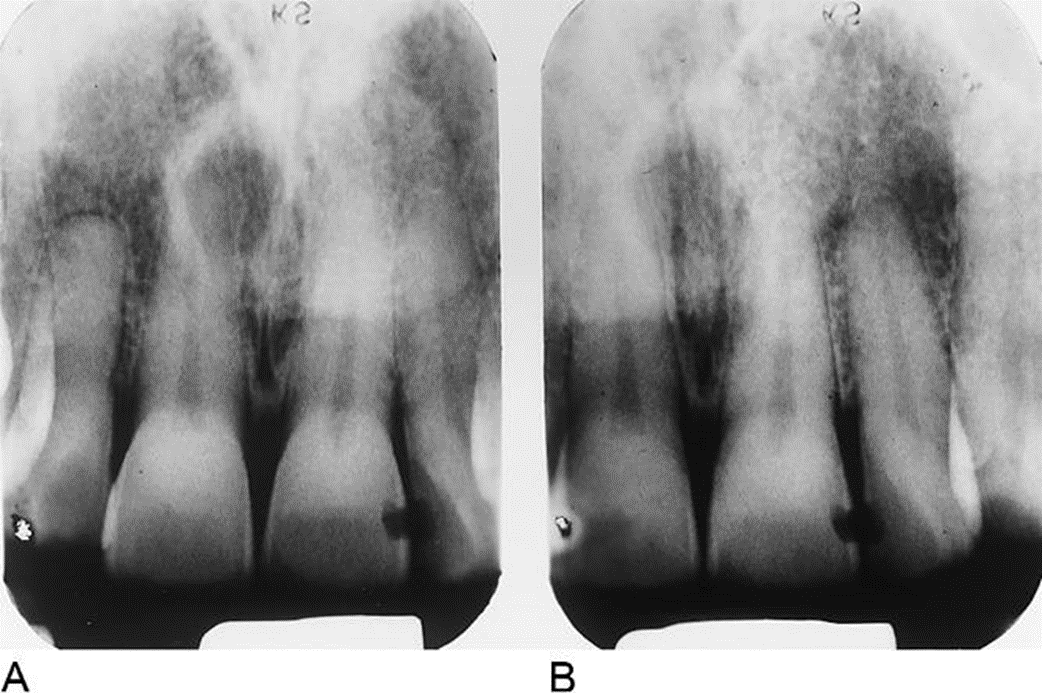

21. What is the most likely diagnosis for these periapical lesions of the mandibular incisors?